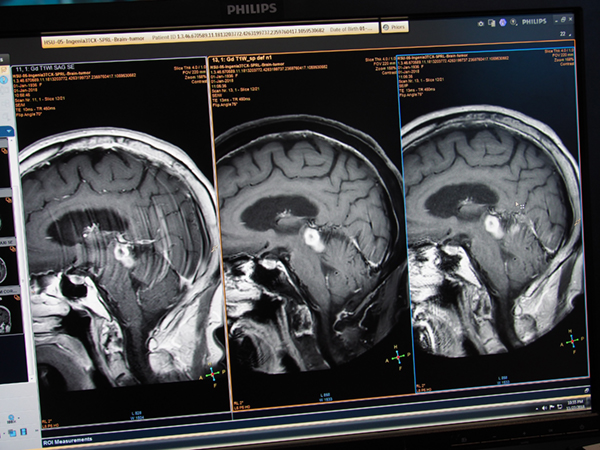

常に進化を続けるMRIアプリケーションも,新しいアプリケーションが複数提供されている。“Diffusion TSE XD”は,EPIベースでの撮像により磁化率の影響で歪みやすかった従来のDWIに対し,TSEベースで撮像することで歪みの少ない画像を取得するアプリケーションである。空気との境目で歪みやすい内耳なども形状の歪みなく撮像できることに加え,体動補正技術“MultiVane”を併用できるため,よりシャープな画像を得ることができる。

また,k spaceをスパイラル状に高速に充填するSpiralシーケンスが実用化され,“Spiral Brain”として紹介された。従来のターボスピンエコー系シーケンスで造影剤を使用した場合,血流の影響でアーチファクトが生じやすかったが,Spiral Brainによりアーチファクトのない画像を短時間で撮像できるようになる。さらに,“mDIXON”を併用することで,脂肪抑制あり/なしの画像を同時に取得することも可能だ。Spiralシーケンスは,Time of Flight(TOF)MRAへも適用可能となっている。

従来のDWI EPI(左),“Diffusion TSE XD”(中央),高空間分解能の“Diffusion TSE XD”(右)

従来の画像(左),mDIXON併用“Spiral Brain”(中央),“Spiral Brain”(右)